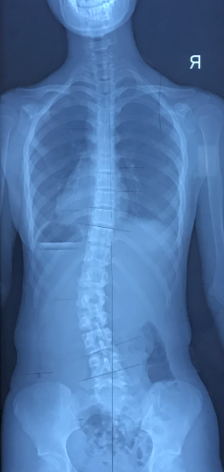

我们还是以常见的腰椎左侧弯为例(图4)。

患者自然站位下的外观跟X光片是相符的,左侧腰切迹较突出,右侧腰切迹较凹陷(图5)。

我们可以让患者左下肢提踵(提高左髋),左髋的抬高会被动地将腰椎推向右侧,使脊柱处于中立位或过矫正的位置(图6)。

或者让患者左腿支撑、右膝屈曲(类似稍息的动作),使右髋降低,也可以起到纠正脊柱侧弯的效果。腰椎右侧弯的患者,同样的思路提高右髋或屈曲左膝即可。